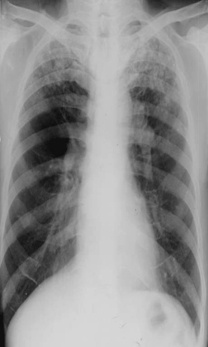

斑片状阴影位于双肺尖,根据公式诊断浸润性肺结核